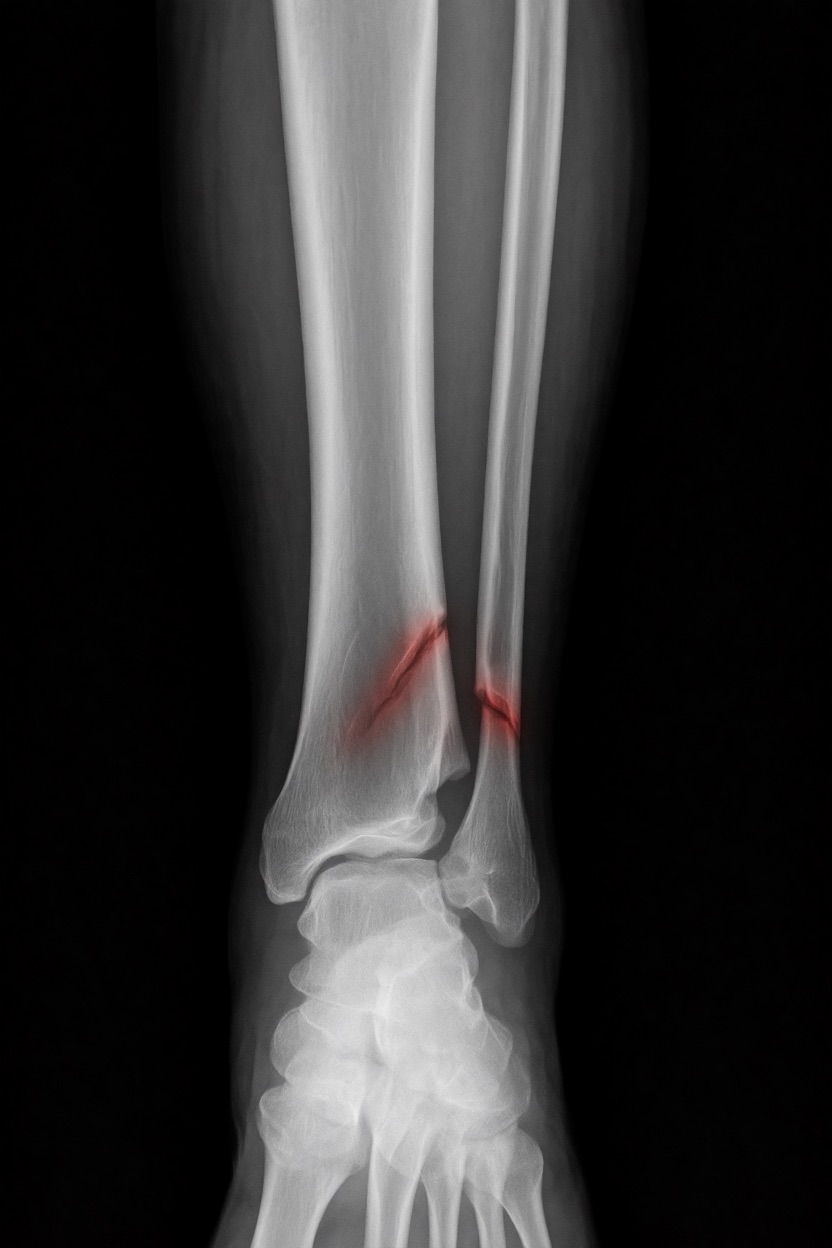

アートや写真の編集用に設計されたFlux Kontextのようなモデルを、医療画像、たとえば「単純な」骨折の赤色マーキングに使用できるか?

即答:面白い結果を出すが、過剰に反応し、医療ツールとしては信頼性に欠ける。これはアイデアを試すためのプロトタイプに過ぎない。

テスト結果:

- 偽陽性 ≈ 24%

- 骨折検出 ≈ 20%

感度モード(検出を優先、ノイズ多め)

- Euler、15ステップ、Karras

- Denoise:1.0

結果:

- 偽陽性 ≈ 80%

- 骨折検出 ≈ 86%

さらに攻撃的な設定(例:rk beta57、Denoise 1.0)では、**偽陽性100%、検出100%**という馬鹿げた結果に:すべてを赤で塗りつぶし、健常部もほぼすべて骨折と誤認する。未経験の目には区別がつかない。

Civitai用に作成した、100% AI生成の合成ミニデータセット(健康なX線10枚、骨折のあるX線10枚)でテスト:

- 健康な骨での偽陽性:100%

- 骨折検出:≈ 45%